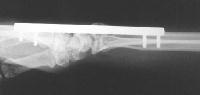

Clinical Example: Distraction plate fixation of distal radius fracture

distal radius fracture

distraction plate